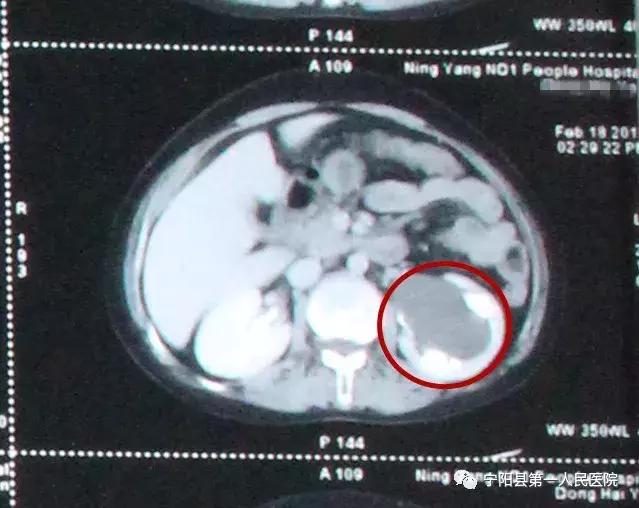

经泌尿外科主任陈强医生诊断以及结合各项检查结果后发现,佟大姐得了“左肾盂旁囊肿”,直径有5CM,大约网球一般大小,需要进行手术治疗。

佟大姐肾盂旁囊肿的位置与肾盂、肾门等人体组织相邻,如果采用穿刺硬化的治疗方法,有可能损伤到肾盂或肾门等其他人体组织结构。如果实施开放手术的话,创口大、术后恢复时间长。